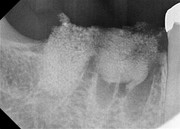

Socket + Implantation 3,5 Jahre Follow up

Nach Entfernung der Zähne 46 und 47, Augmentation DentOss fein, Adaptationsnähte, 6 Tage danach, Implantation nach 5 Monaten und ZE 45, 46 mit Zirkonkronen.Röntgenkontrolle nach einem Jahr und klinische Situation. 3,5 Jahre nach Socket.